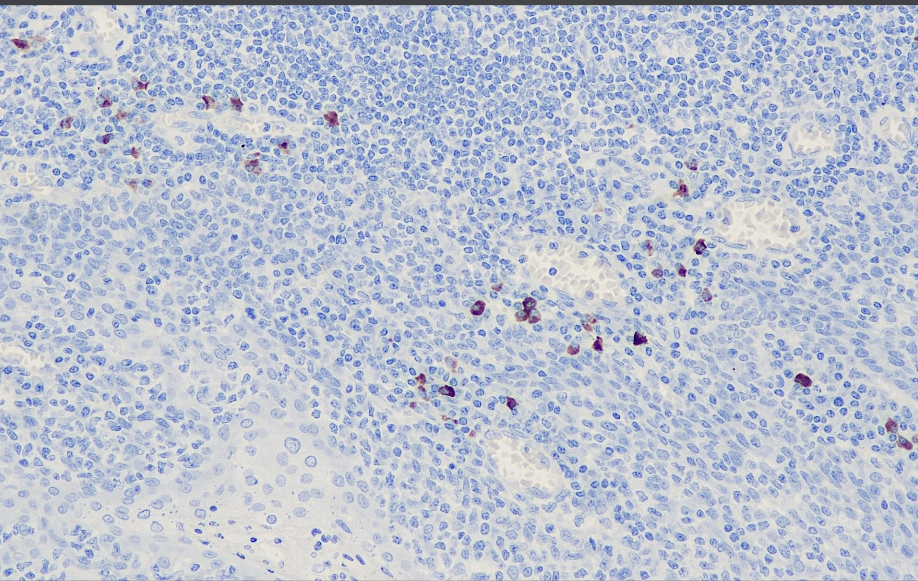

克隆号:EP138

细胞定位:细胞质

阳性对照: 扁桃体/阑尾

主要用于检测与IgG4相关的硬化性疾病,组织病理学特征为病变组织弥漫性淋巴浆细胞浸润、纤维化、阻塞性静脉炎以及大量IgG4阳性的浆细胞,该病对激素治疗有效、预后好。

IgG4抗体试剂可与IgG4分子抗原特异性结合,含IgG4抗体试剂的免疫组化试剂盒适用于IgG4相关疾病(如自身免疫性胰腺炎、米库利茨病)的精准诊断。